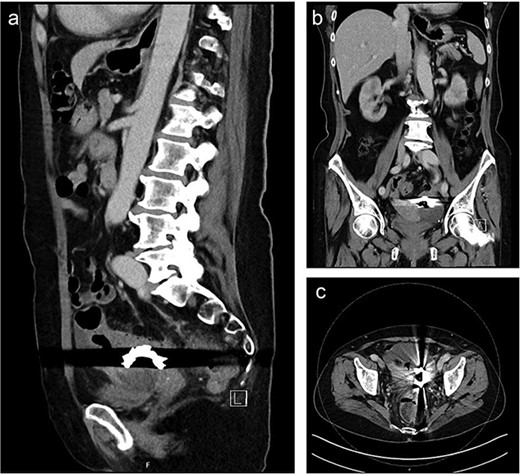

Computed tomography (CT) showed a foreign body in the sigmoid colon with adjacent fluid collection (Fig. 1). Due to vesical air inclusions, a sigmoido-vesical fistula was suspected. When further asked, the patient recalled that she had lost her denture 3 months ago at the Christmas market in December 2022. Colonoscopy revealed the impacted foreign body at 35 cm from anal verge with swollen and scarred stenosis of the sigmoid colon (Fig. 2). Endoscopic retrieval of the metal denture was not possible.

Sagittal (a), coronal (b) and axial slice (c) of a preoperative CT scan showing the ingested denture in the sigmoid colon with adjacent fluid collection and vesical air inclusions.